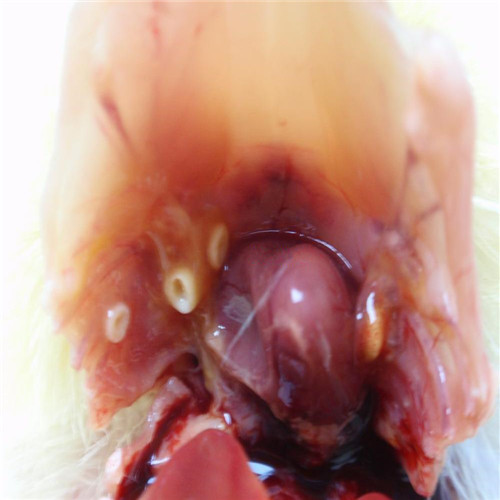

呼吸道感染者扁桃體發炎切除物